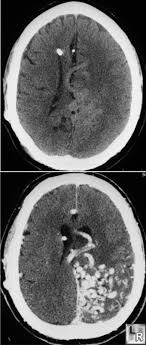

Unenhanced And Enhanced Axial Cts Of Brain Shows A Large Serpiginous Avm Adjacent To The Tentorium Radiology Imaging Radiology Interventional Radiology